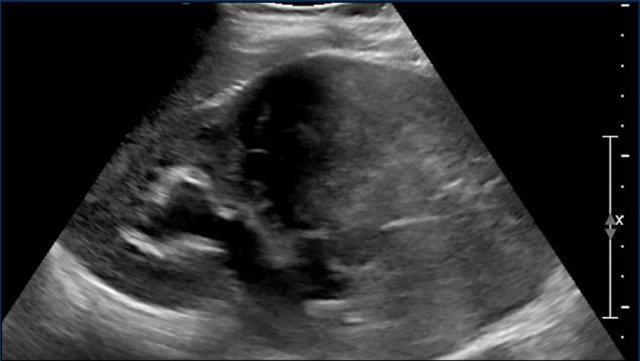

Image

A nine-year-old boy presented with severe hematuria.

On palpation a left abdominal mass was found.

On ultrasound a predominantly solid mass was seen which seemed to invade the dilated collecting system.

On imaging renal cell carcinomas can present in many different ways.

They can appear more solid or have cystic elements and may be homogeneous, or rather heterogeneous.

Hemorrhage can occur and they may contain fat.

Relative small tumor size and prominent peripheral vessels suggests a RCC.

Imaging is essential for staging and a combination of ultrasound, CT and MRI is used.

video

MRI nicely demonstrates the mass in the left kidney. Note the large collateral veins.

Because of heavy hematuria a left nephrectomy was performed.

Pathology showed a RCC which was completely resected.